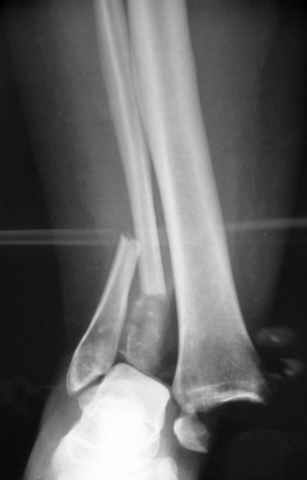

A propos fibular fixation if one is eager to stabilize it separately. In the fracture pattern a way of closed fixation by V-shaped stressed wire (advanced by colleagues from Moscow, prof. Lazarev A.F. et al.) must be excellent. We use indirect closed reduction by the external fixator. Example attached, that fibular fracture is even more suitable for plating but the wire did the job.

I agree with primary spanning ex-fix, but IMHO some days later it is worth to attempt to restore tibial articular surface as much as possible, using ligamentotaxis and joystick wires under image intensifier. Maybe even put autografts through limited incisions.